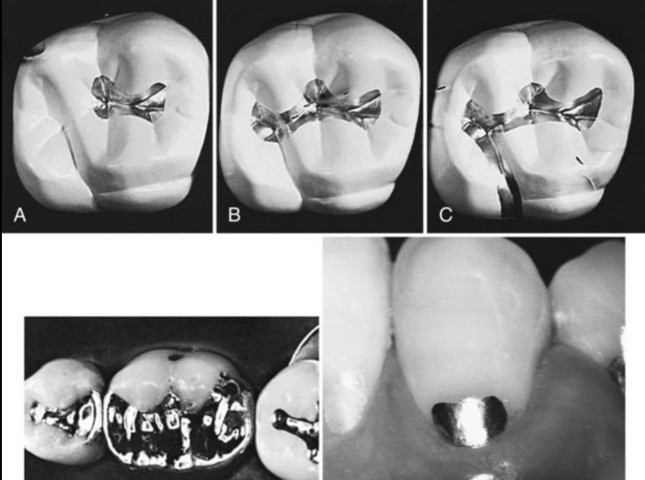

Процесс создания пломбы прост: порошок из нескольких металлов, чаще всего серебра и олова, смешивают с жидкой ртутью. Ртуть связывает эти металлы, превращая их в густую пасту. Затем стоматолог наносит эту смесь в кариозную полость, придавая ей нужную форму. Через некоторое время пломба затвердевает и слегка расширяется, надежно фиксируясь в зубе.

Однако у такого метода лечения есть и очевидные минусы. Раньше стоматологи замешивали пломбы вручную, из-за чего и врачи, и пациенты подвергались воздействию паров ртути. Сегодня для этого используются специальные аппараты, но стоит ли беспокоиться о наличии ртути в пломбах?